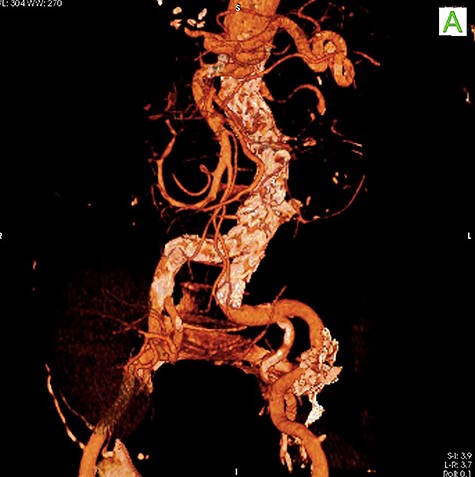

Given the rapid decompensation in the patient, a simultaneous liver-kidney transplant was proposed, but because the accepted diameter of aneurysm for surgical management is 5.5 cm and higher [1], it was decided to closely follow-up with the patient post-transplantation. The liver was transplanted using the piggy-back technique, inferior vena cava was anastomosed side-to-side, and portal veins and hepatic arteries were anastomosed end-to-end. The donor kidney was placed in the right iliac fossa with anastomosis of the right internal iliac artery and vein in an end-to-end fashion. The patient then had an uncomplicated post-operation course and was discharged with an immunosuppressive regimen. One month later, the patient came to the emergency room with severe abdominal pain. To rule out possible aneurysm rupture, an emergent CT scan with contrast was performed; however, the findings were compatible with an infrarenal aortic aneurysm with eccentric mural thrombosis. In addition, the aneurysm had grown in size and had a diameter of 5.2*6.5 (Fig. 2).